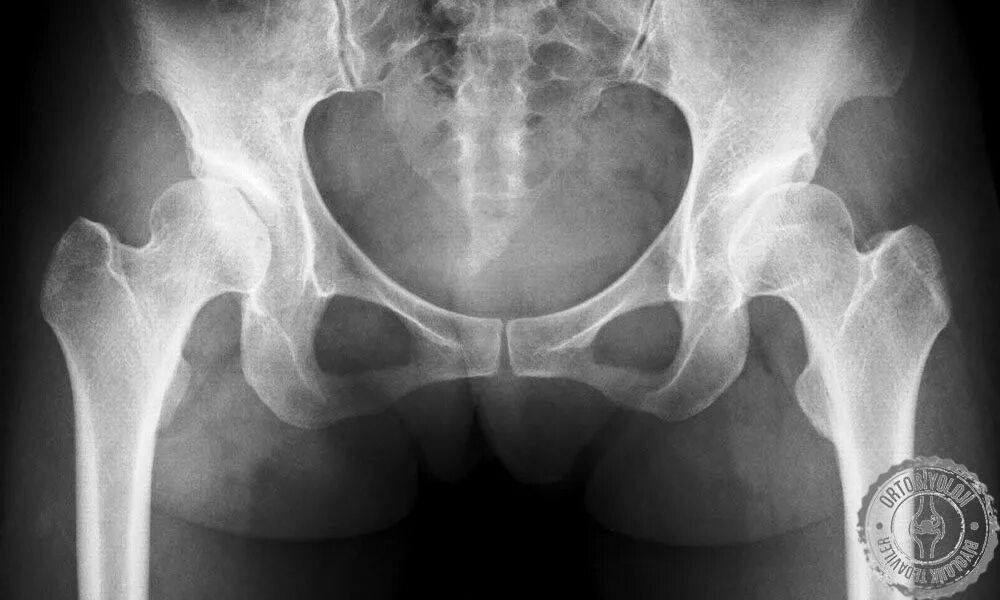

Аваскулярный некроз тазобедренного сустава